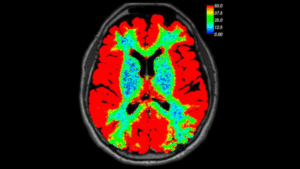

COVID Brain Perfusion

Assess Cerebral Blood Flow in Long COVID Patients

This project assesses cerebral blood flow in long COVID patients as well as examine the neural correlates of cognitive dysfunction after COVID-19. We expect that survivors of mild to moderate COVID-19 will demonstrate significantly lower executive-attention network connectivity compared to non-infected controls and that this will correlate with cognitive dysfunction. We are specifically focusing on mechanism underlying cognitive impairment in COVID-19 associated with cerebral perfusion

This work is in collaboration with Dr. Shelli Kesler